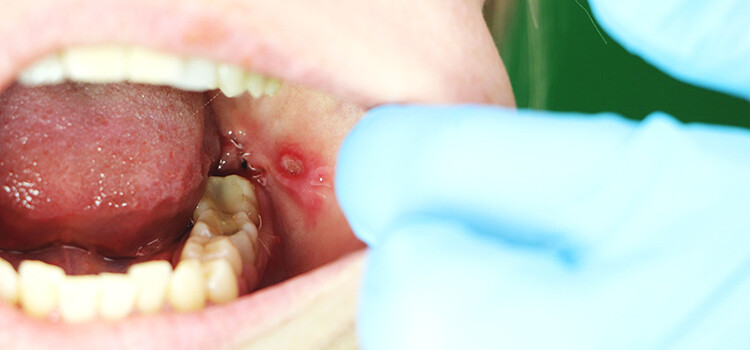

You feel it coming on: A spot in your mouth starts to burn or tingle, and you know what's about to happen. By tomorrow you'll have a nagging sore cratered into the lining of your cheek. Aphthous ulcers afflict 20% of the population, recurring intermittently and often without a distinct pattern. After a week or two, the pain disappears and your mouth feels whole again.

Aphthous ulcers are sometimes confused with cold sores, but they're only related by their discomfort and proximity to each other. Cold sores occur on the lips and surrounding skin as a result of the Herpes Simplex Virus. Aphthous ulcers don't have such a clear cause. These lesions show up on movable tissue surfaces inside the mouth and may be difficult to pin to a single instigator. We understand that the body's immune system sends inflammatory cells into an area and destroys its own tissue, but what triggers the assault?